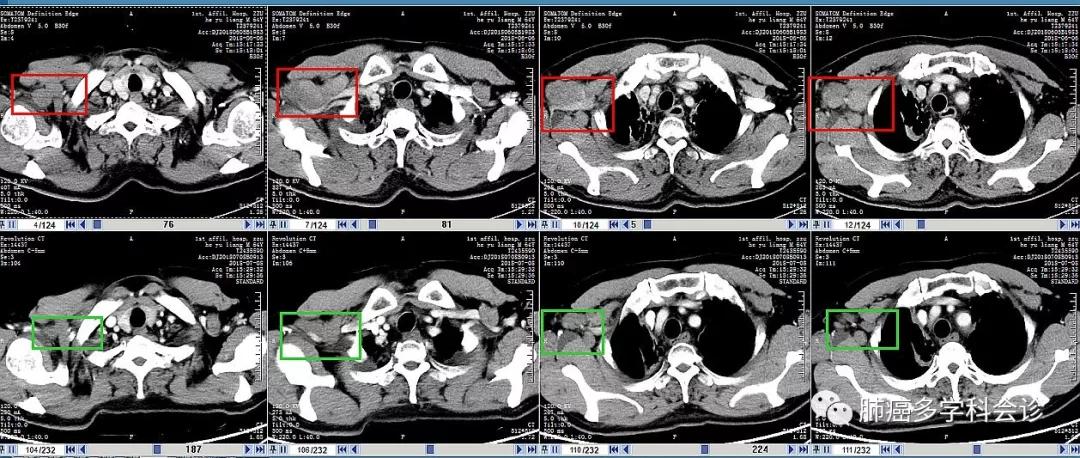

以下是2周期治疗前(每图上行,2018-06-06)和治疗后(每图下行,07-08)腋窝和纵隔转移淋巴结大小等的比较: